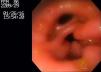

Se realizó transfusión de un paquete globular, así como endoscopia al día siguiente de su ingreso, por cuadro compatible con sangrado de tubo digestivo alto, encontrándose como hallazgos: hernia hiatal de 3cm sin esofagitis, gastritis erosiva crónica activa de fondo, cuerpo y antro (fig. 1) secundaria a AINE y asociada a Helicobacter pylori por biopsia, a la cual se realizó prueba rápida de la ureasa y posteriormente fue confirmada por análisis histopatológico, así como presencia de píloro doble adquirido secundario a enfermedad ácido-péptica (fig. 2); no hubo evidencia de tumores u otras lesiones asociadas (video). Se inició esquema de erradicación para H. pylori con amoxicilina y claritromicina durante 14 días, asociados a inhibidor de bomba de protones durante 6-8 semanas con buena respuesta al manejo médico. Se realizó control endoscópico a las 8 semanas, el cual mostró remisión de la gastropatía erosiva y de los síntomas posteriormente al manejo médico, así como biopsias con H. pylori negativo.

La endoscopia es generalmente el método de visualización preferido. En la mayoría de los casos, el píloro doble se encuentra incidentalmente durante la evaluación endoscópica de dolor abdominal, anemia o melena como en nuestra paciente. En la endoscopia, se visualiza un canal accesorio de dimensiones variables sin movimientos peristálticos. El canal accesorio puede medir de unos pocos milímetros a varios centímetros.